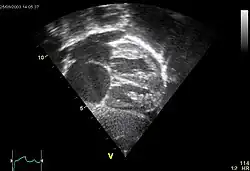

Ultraschall

Goldstandard zur Detektion ist die transösophagale Ultraschalluntersuchung mit einem nicht lungengängigen Kontrastmittel.[21] Manchmal ist bereits mit der Farbdopplerechokardiographie von transthorakal eine ausreichend gute Beurteilung des ASD und des Blutflusses durch den Defekt möglich.

Liegt der Defekt in der Mitte der Vorhofscheidewand, kann bei 70 % der Patienten ein Verschluss mit einem Doppelschirmchen durchgeführt werden. Dieses wird im Rahmen eines Herzkathetereingriffes eingesetzt. Die Durchführung kann in der Mehrzahl der Fälle unter transösophagealer echokardiografischer Kontrolle erfolgen. In Einzelfällen ist eine angiografische Darstellung erforderlich.